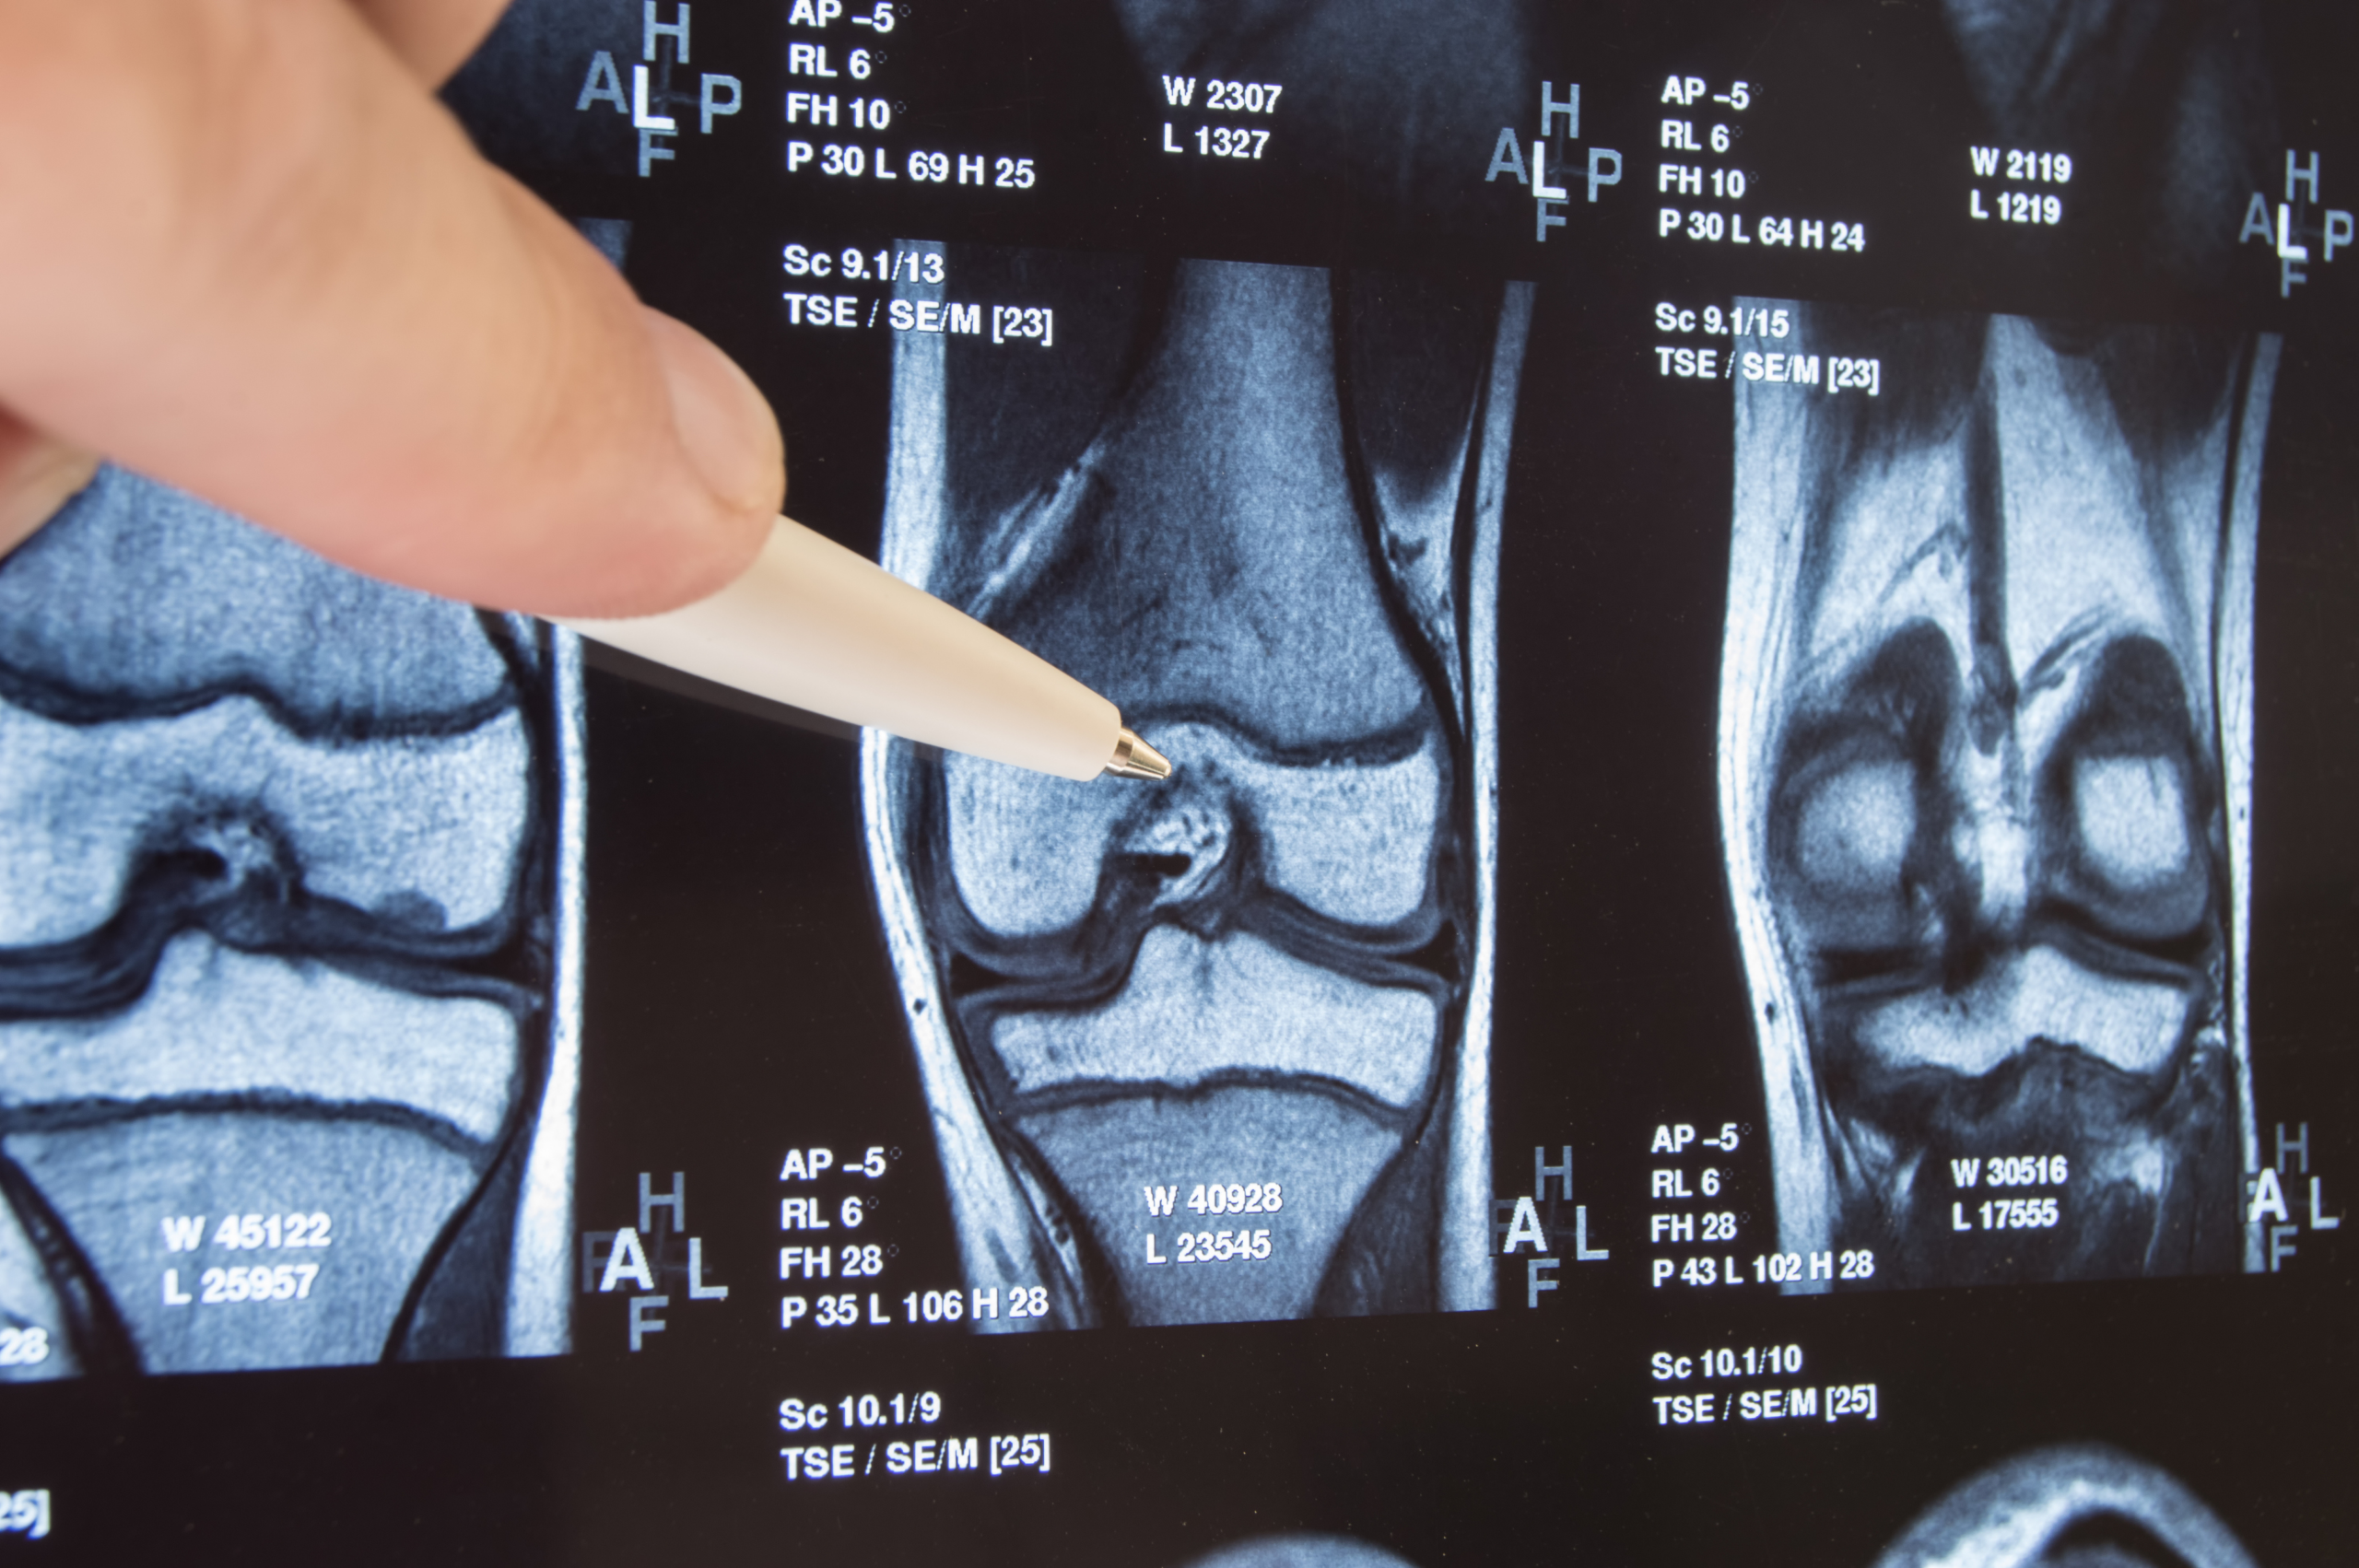

Knee replacement surgery (also called knee arthroplasty) removes damaged bone and cartilage from the knee joint and replaces it with an artificial implant made of metal and medical-grade plastic. It is one of the most frequently performed and well-studied orthopedic procedures in the world, with success rates consistently above 95% at accredited centers.

Your final surgical plan, including implant choice (Smith & Nephew, Zimmer Biomet, or Stryker, depending on your anatomy) and surgical approach, is confirmed by your surgeon at the in-person pre-op consultation in Medellín.

X-ray or MRI evidence of significant joint deterioration or cartilage loss